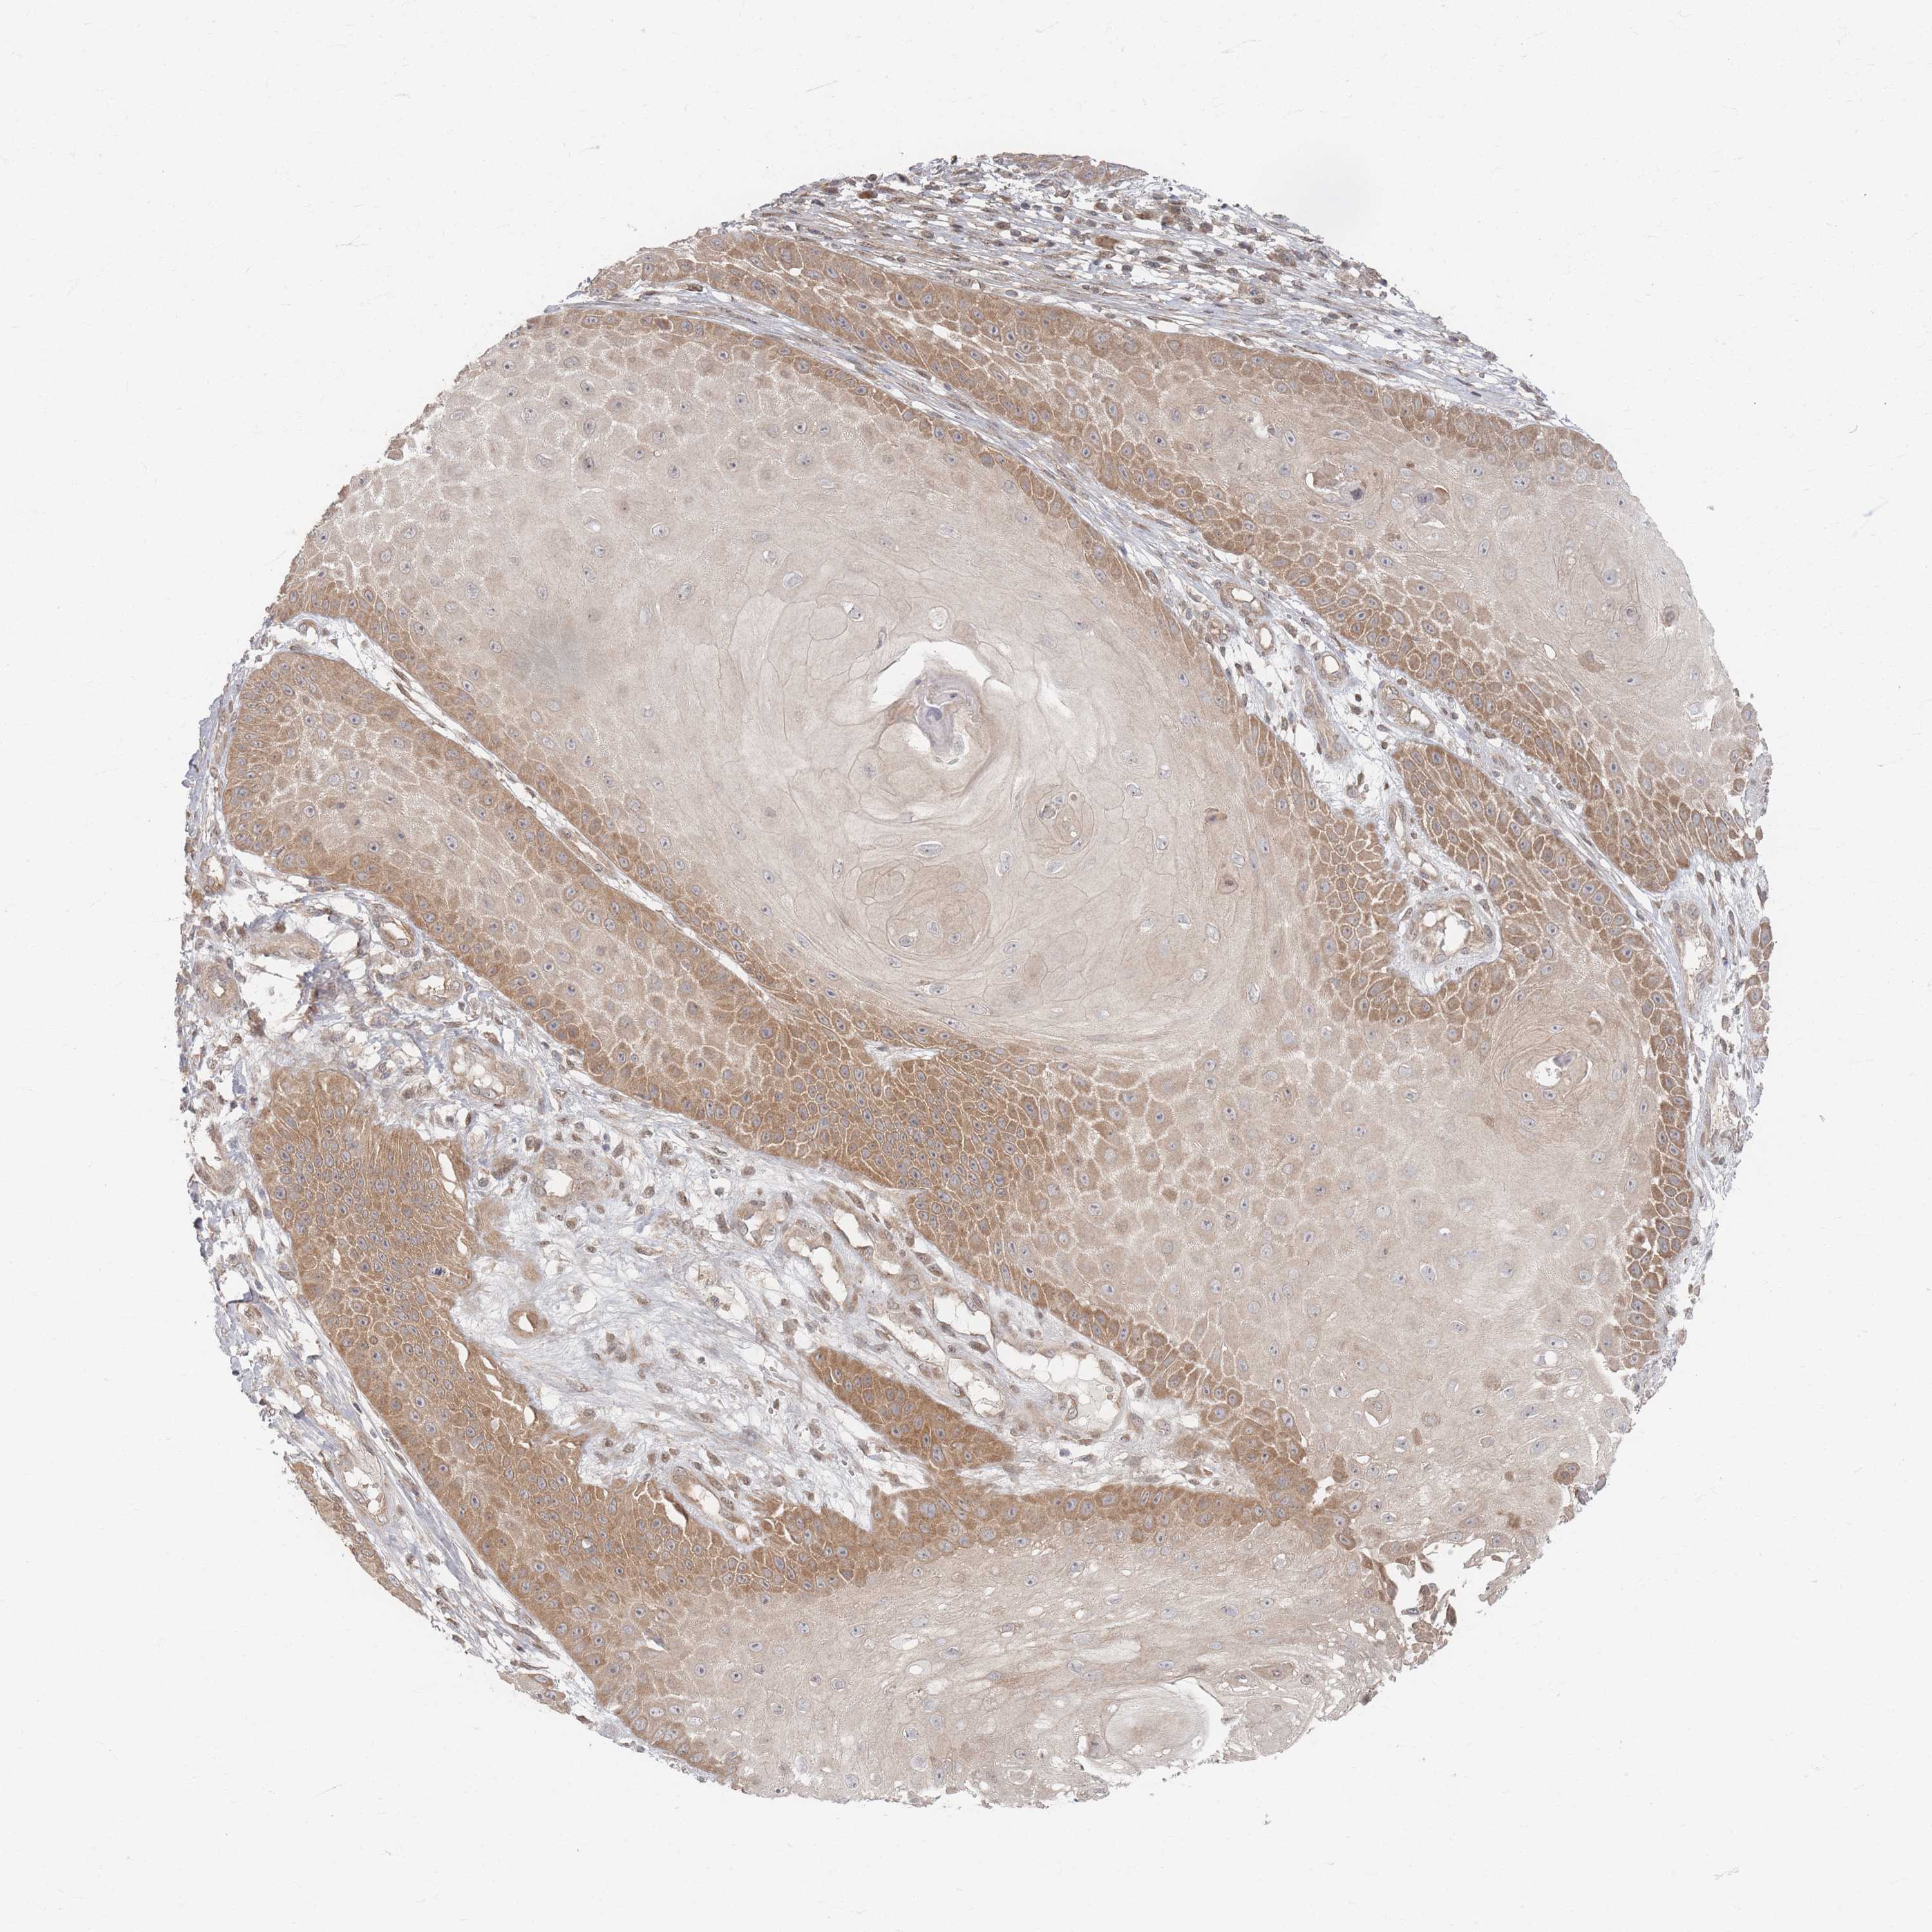

CANCER SKIN CANCER Show tissue menu

Basal cell and squamous cell cancer

SKIN CANCER - Protein expressioni

A mouse-over function shows sample information and annotation data. Click on an image to view it in a full screen mode. Samples can be filtered based on level of antibody staining by selecting one or several of the following categories: high, medium, low and not detected. The assay and annotation is described here.

Each image is clickable and will lead to virtual microscopy that enables deeper exploration of all samples and also displays staining intensity scores, fraction scores and subcellular localization as well as patient and tissue information for each sample.

Antibody HPA040512

Squamous cell carcinoma, NOS